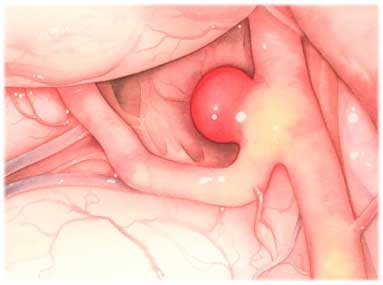

Мешотчатая аневризма представляет собой локальное расширение стенки сосуда, которое имеет форму мешочка. Врачи отмечают, что данное состояние чаще всего возникает в области артерий головного мозга и может быть опасным, так как существует риск разрыва аневризмы. Симптомы могут варьироваться в зависимости от размера и расположения аневризмы. На ранних стадиях заболевание может протекать бессимптомно, однако при увеличении аневризмы пациенты могут испытывать головные боли, нарушения зрения, а также неврологические симптомы, такие как слабость или онемение в конечностях. Важно, чтобы пациенты, у которых есть предрасположенность к аневризмам, проходили регулярные обследования, так как ранняя диагностика может значительно повысить шансы на успешное лечение. Врачи подчеркивают необходимость обращения за медицинской помощью при появлении настораживающих симптомов.

Что такое мешотчатая аневризма

Как уже упоминалось ранее, мешотчатая аневризма головного мозга представляет собой образование, напоминающее маленький мешок. Обычно такие аневризмы располагаются в следующих областях:

Важно подчеркнуть, что у небольшого числа пациентов может наблюдаться множественное поражение сосудов, когда аневризмы располагаются в нескольких местах одновременно. Со временем аневризма окончательно формируется, приобретая свод и шейку. Истончение эластичных слоев сосудистой стенки и замещение гладкомышечной мускулатуры могут привести к разрыву аневризмы.